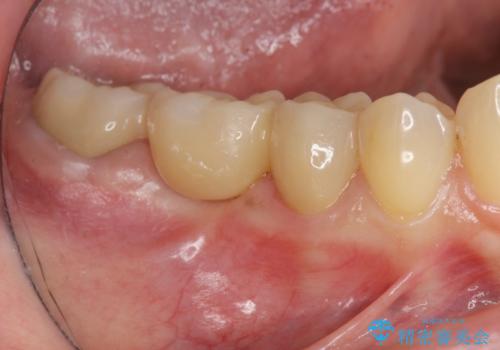

欠けた前歯を綺麗にしたい

- 「欠けてしまった前歯のコンポジットレジン修復をくり返していたが、すぐ外れてしまい困っている。」

、と前歯の欠けの改善を求めて来院されました。

噛み合わせが深く、前歯の突き上げが大きいため欠けの繰り返しを防ぐべくセラミッククラウンによる補綴を行うこととしました。

審美性の改善を達成することができました。